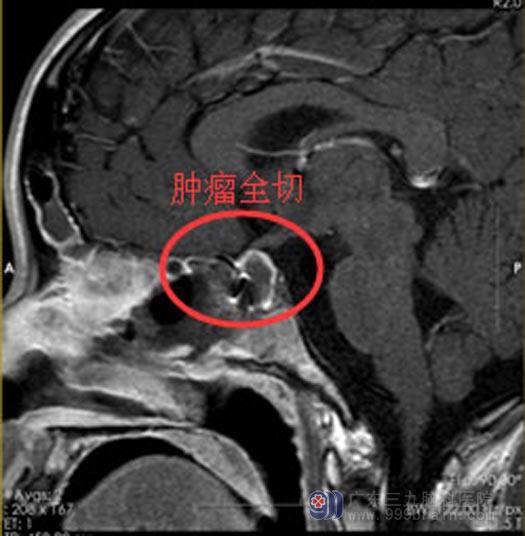

经小莹的家长同意后,实施了“内镜经鼻蝶鞍区垂体瘤切除术”,该手术具有创伤小,恢复快的特点。手术过程非常顺利,导航精确定位,切开硬脑膜后,见到了灰白色肿瘤流出,囊肿组织质硬,垂体左侧和肿瘤黏连明显,沿肿瘤薄膜全切肿瘤。